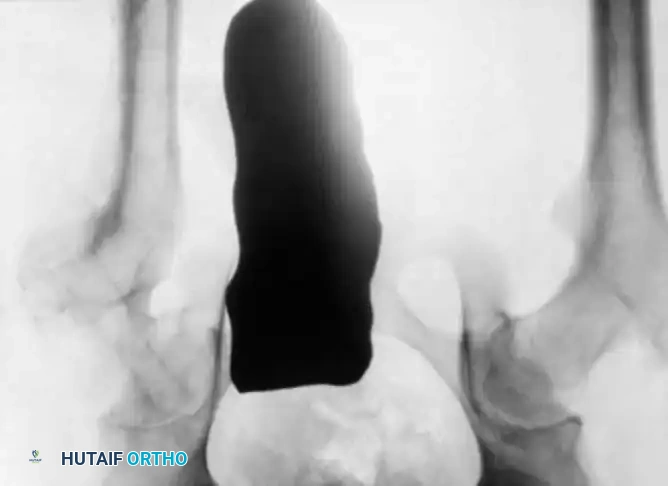

Radiographic Gallery: Diagnosis and Evaluation

Associated Surgical & Radiographic Imaging